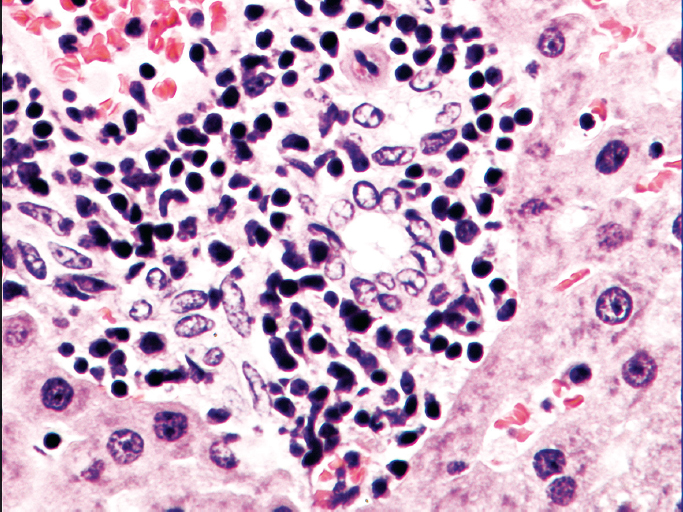

Рис. 1. Неалкогольная жировая болезнь печени (аутоптат печени, окраска гематоксилином и эозином, увел. ×40). Мононуклеарная инфильтрация

Fig. 1. Non-alcoholic fatty liver disease (liver autopsy, Hematoxylin-eosin staining, magnification ×40). Mononuclear cell infiltration

Гистологическое исследование также подтвердило различную степень выраженности морфологических изменений в экспериментальной и контрольной группах. У животных группы НАЖБП на гистологических препаратах печени регистрировали мононуклеарную инфильтрацию, гиперемию синусоидов, нарушение балочной структуры (рис. 1). В экспериментальной группе с НАЖБП наблюдалась крупнокапельная жировая дистрофия, которая характеризовалась наличием крупных липидных капель в цитоплазме гепатоцитов со смещением ядра к периферии клетки.